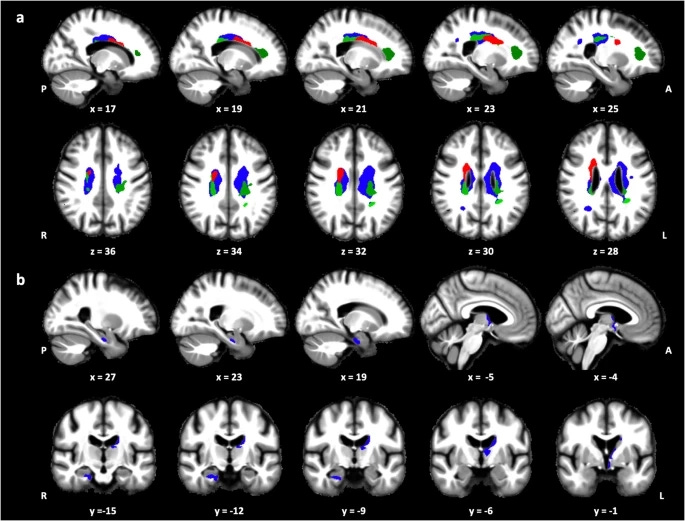

In a 2024 study of healthy older adults, researchers tracked REM across a 40-hour, tightly controlled lab stay with repeated naps and mapped it to each person’s circadian clock, using melatonin release timing to define their circadian sleep phase (not clock time).

Instead of just asking “how many minutes of REM did they get,” they measured how strongly REM was concentrated at each person’s circadian sleep phase versus appearing across the rest of the 24-hour day — a measure they called circadian REM amplitude.

People whose REM was more strongly pulled into their circadian sleep phase had healthier-looking white matter and deeper brain regions (including hippocampus and thalamus) on quantitative MRI.

Those with a flatter REM rhythm—less of a circadian-phase peak (lower circadian REM amplitude)—showed MRI brain microstructural differences consistent with age-associated tissue variation, even after adjusting for overall REM%.

This tells us that it’s not only how much REM you get, but how tightly REM expression is coupled to your circadian sleep phase that relates to brain health.